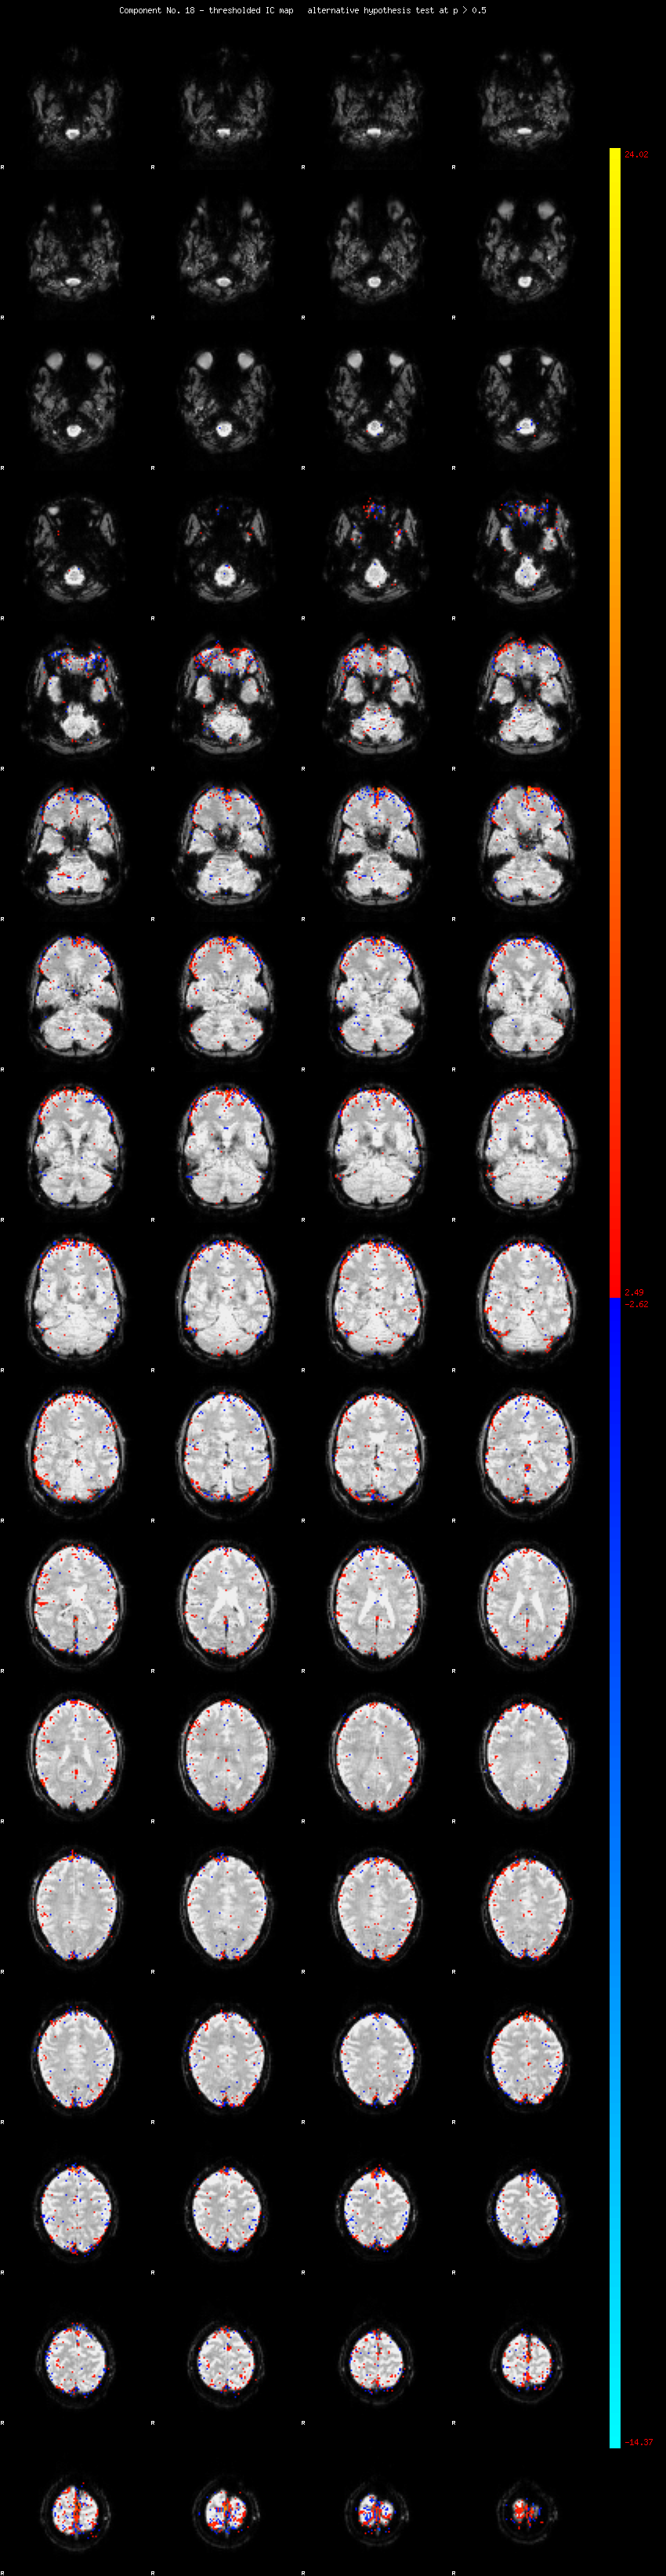

MELODIC Component 18

1.44 % of explained variance;     0.95 % of total variance

MMfit